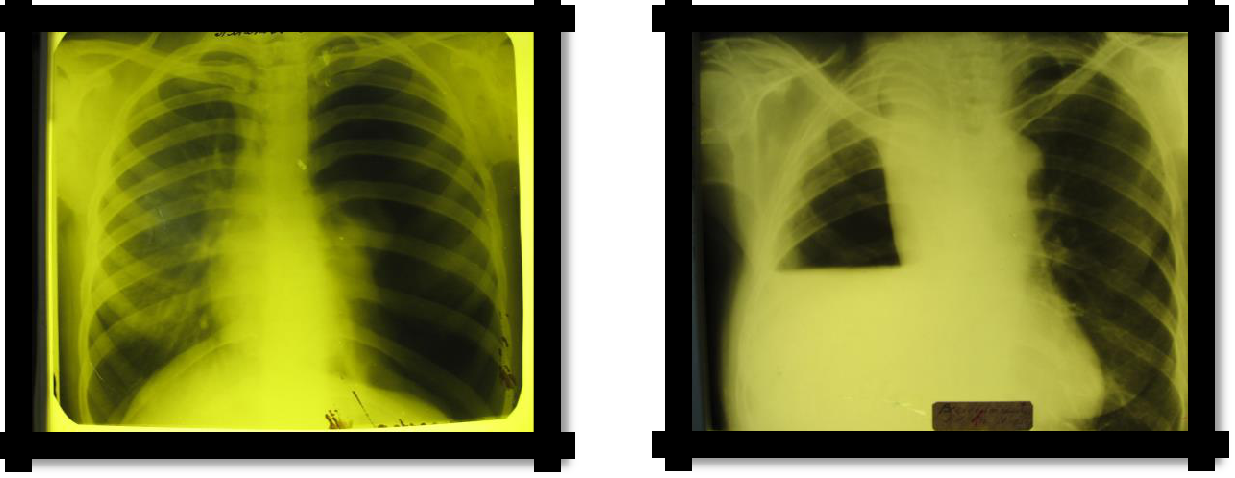

1. X-ray: intercostal space narrowed, homogeneous darkening in the atelectasis and mixing of the mediastinum to the affected side (Goltsknecht-Jacobson symptom), high standing of the diaphragm.

Pic 2.9 Obstructive atelectasis